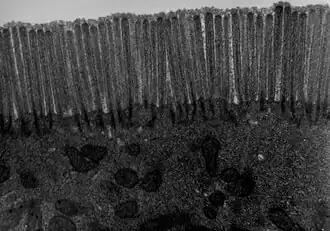

The interior surface of the jejunum—which is exposed to ingested food—is covered in finger–like projections of mucosa, called villi, which increase the surface area of tissue available to absorb nutrients from ingested foodstuffs. The epithelial cells which line these villi have microvilli. The transport of nutrients across epithelial cells through the jejunum and ileum includes the passive transport of sugar fructose and the active transport of amino acids, small peptides, vitamins, and most glucose. The villi in the jejunum are much longer than in the duodenum or ileum.

- The villi of the jejunum look like long, finger-like projections, and are a histologically identifiable structure.

Transmission electron microscope (TEM) image of human jejunum -

TEM image of mouse jejunum (14,000-fold magnification) -